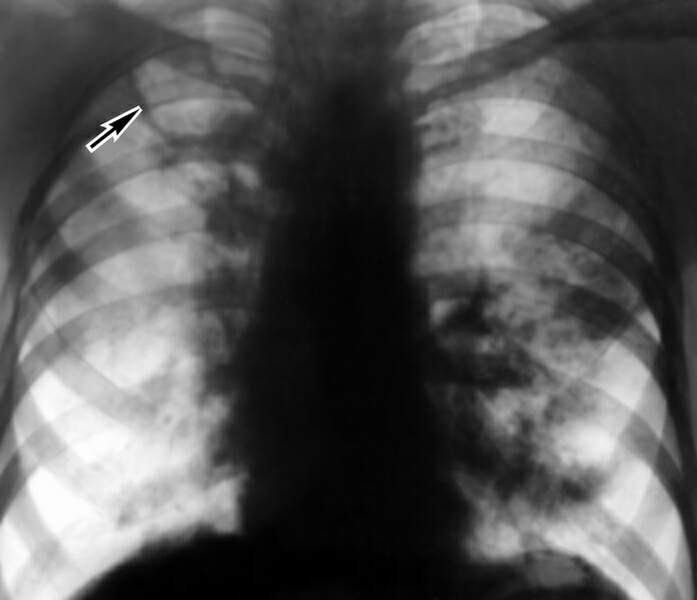

Фиброзно-кавернозный туберкулез легких (рентгенограмма)